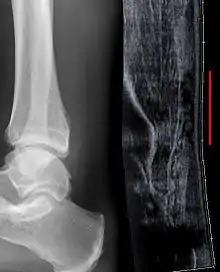

التصوير

يمكن أن يستخدم تخطيط الصدى العضلي الهيكيلي لتحديد سماكة الوتر، طبيعته، ووجود تمزق. يتم عن طريق إرسال ترددات صوت عالية شديدة خلال الجسم. تنعكس بعض من هذه الأصوات إلى الفراغات بين السائل بين الخلوي والنسيج الرخو أو العظم. هذه الصور المنعكسة يمكن أن تحلل وتتم حوسبتها إلى صورة. تلتقط هذه الصور في الزمن الحقيقي وتكون مفيدة جداً في تتبع حركة الوتر وتصور الإصابات أو التمزقات المحتملة. هذه الأداة تسهل عملية اكتشاف الأضرار الهيكلية للأنسجة الرخوة، وهي طريقة مناسبة لاكتشاف هذا النوع من الإصابات. هذه الوسيلة من التصوير غير مكلفة، ولا تشمتل على أي إشعاعات مؤينة، وهي موثوقة جداً إذا كانت بأيدي مهرة من أخصائيي تخطيط الصدى.

تصوير الرنين المغناطيسي يمكن أن يستخددم لتمييز التمزقات غير المكتملة من كونها اضمحلال للوتر العقبي، يمكن أيضاً للتصوير بالرنين المغناطيسي التمييز بين التهاب مجاورات الوتر، والتهاب الوتر المزمن، والالتهاب الكيسي. هذه التقنية تستخدم حقلا مغناطيسيا منتظما قويا لاصطفاف الملايين من البرتونات التي تمر عبر الجسم. هذه البروتونات يتم قذفها لاحقاً مع موجات الراديو التي تبعد بعض منها خارج الانتظام. عندما تعود هذه البروتونات تنبعث منها موجات راديو خاصة فريدة بها ويمكن أن تحلل من خلال الحاسوب إلى شكل ثلاثي الأبعاد لصنع صورة مقطعية عرضية حادة للمنطقة المعنية. يمكن أن يوفر التصوير بالرنين المغناطيسي تباينا فريدا للأنسجة الرخوة للصورة ذات الجودة العالية ليسهل على الاخصائيين اكتشاف الانقطاعات والتمزقات وغيرها من الإصابات.

التصوير الشعاعي يمكن أن يستخدم أيضاً لتعرف انقطاعات وتمزقات الوتر العقبي بشكل غير مباشر. التصوير الشعاعي يستخدم الأشعة السينية لتحليل نقطة الإصابة. لا تكون هذه الوسيلة فعالة جداً في تحديد إصابات النسيج الرخو. تنشأ الأشعة السينية عندما تصطدم الإلكترونات عالية الطاقية بمصدر معدني. يتم الحصول على صور الأشعة السينية من خلال استخدام خصائص التوهين المختلفة للأنسجة ذات الكثافة (مثال: الكالسيوم في العظم) و أنسجة أقل كثافة (مثال: العضلات) عندما تمر هذه الأشعة من خلال النسيج وتلتقط على فيلم. يتم اللجوء للأشعة السينية عامة لتحسين تصور الأجسام ذات الكثافة مثل العظم، وأما النسيج الرخو فيبقى نسبياً غير متمايز في الخلفية. التصوير الشعاعي لديه دور ضئيل في تقييم إصابة الوتر العقبي وذو فائدة أكثر لاستبعاد الإصابات الأخرى مثل الكسور العقبية.[6]